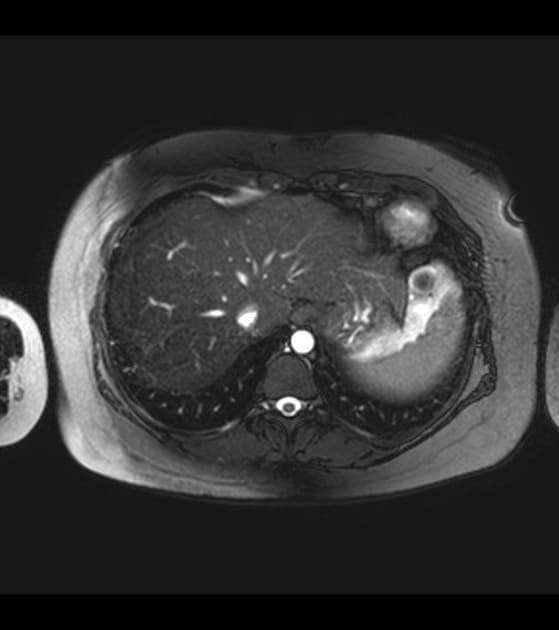

Axial T2

MRI•Axial T2•1 / 4

Ca bệnhBệnh cơ tim phì đại đỉnh không tắc nghẽn (hội chứng Yamaguchi)

Bệnh cơ tim phì đại đỉnh không tắc nghẽn (hội chứng Yamaguchi)

Tim

- Thấy hình ảnh phì đại cơ tim rõ rệt ở thành bên trái thất trái, với sự dày cơ tâm thất đáng kể tại đỉnh tim và hẹp đáng kể trong thì tâm thu.

Bệnh cơ tim phì đại đỉnh không tắc nghẽn (apical non-obstructive hypertrophic cardiomyopathy - Yamaguchi hypertrophy)

Bệnh cơ tim phì đại đỉnh không tắc nghẽn, còn gọi là hội chứng Yamaguchi, là một dạng biến thể hình thái của bệnh cơ tim phì đại, chủ yếu ảnh hưởng đến đỉnh thất trái mà không có tắc nghẽn đoạn ra thất trái. Bệnh lần đầu được mô tả ở Nhật Bản và phổ biến hơn ở các quần thể châu Á. Các phương tiện hình ảnh như siêu âm tim và cộng hưởng từ tim cho thấy hình ảnh dày thành đỉnh rõ rệt, thường có hình dạng giống 'cái xẻng' ở thất trái trong thì tâm trương. Mặc dù không tắc nghẽn, bệnh nhân vẫn có thể gặp các triệu chứng như đau ngực, khó thở hoặc rối loạn nhịp do rối loạn chức năng tâm trương hoặc thiếu máu vi mạch. Dấu hiệu điện tâm đồ đặc trưng là sóng T âm lớn ở các chuyển đạo trước tim giúp phân biệt với các nguyên nhân khác gây phì đại đỉnh hoặc bệnh tim thiếu máu cục bộ. Tiên lượng dài hạn thường thuận lợi, nhưng nguy cơ đột tử do tim, dù hiếm, vẫn cần được theo dõi.